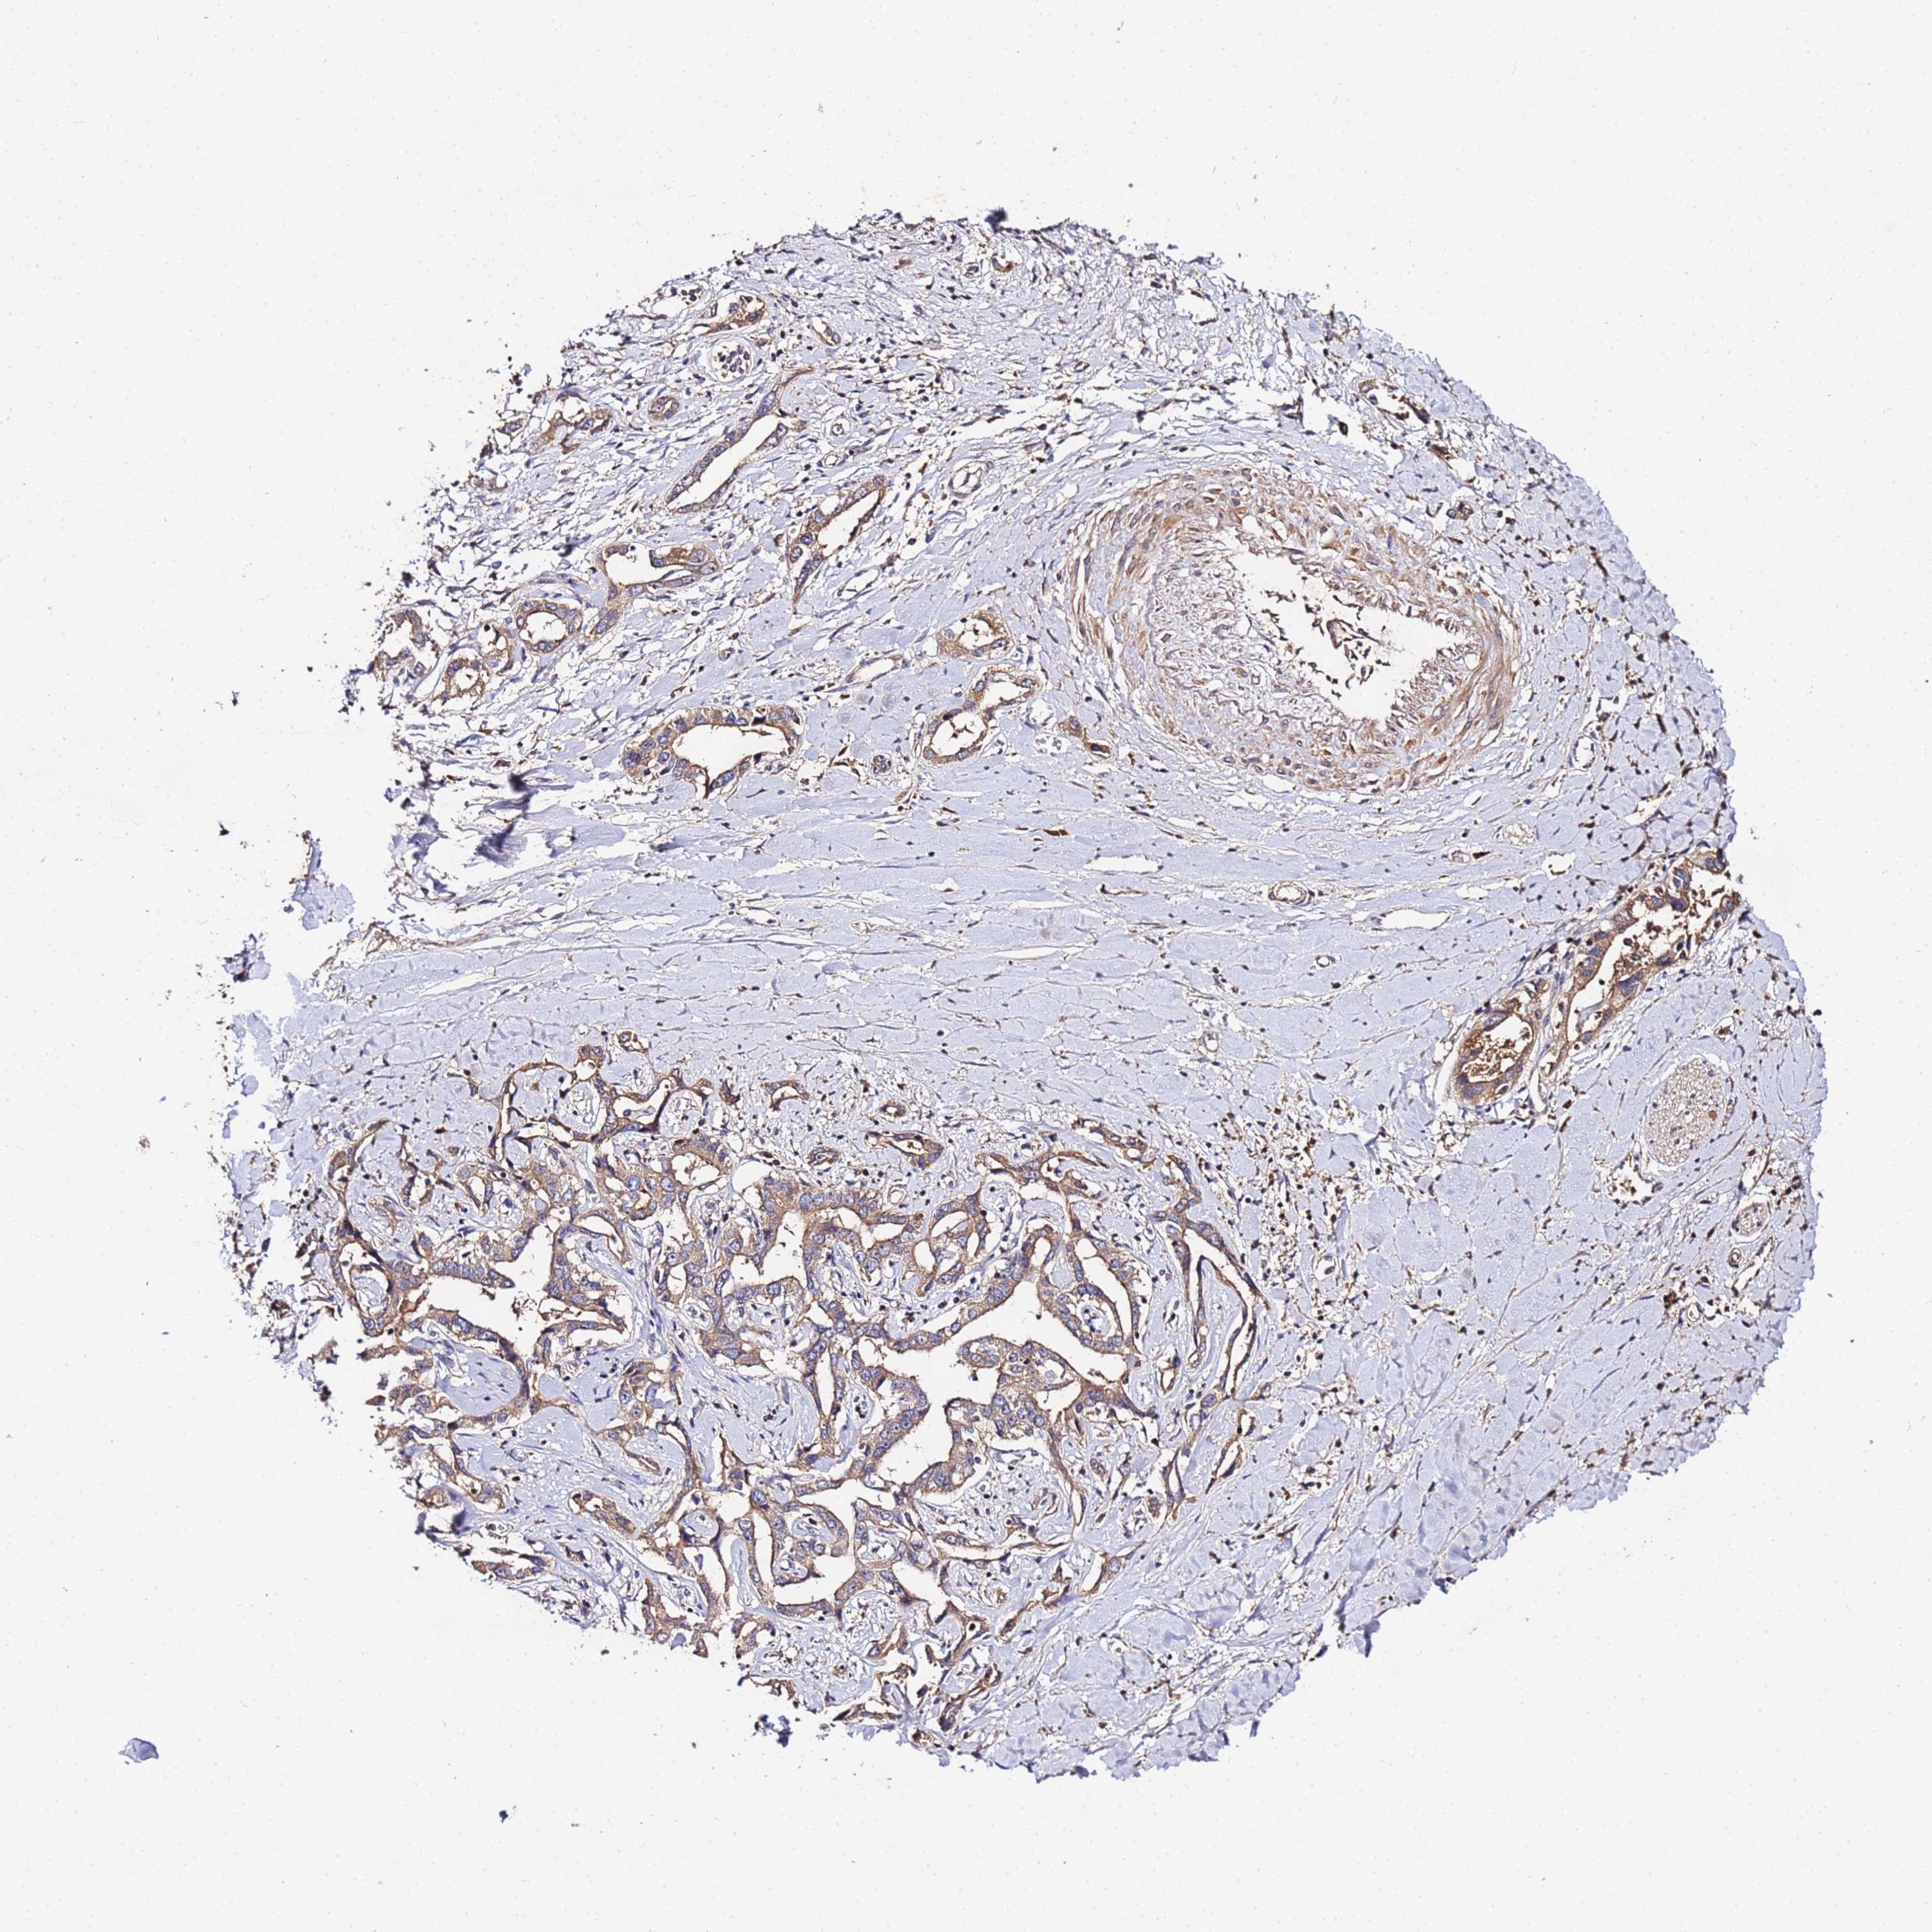

LIVER CANCER - Protein expressioni

A mouse-over function shows sample information and annotation data. Click on an image to view it in a full screen mode. Samples can be filtered based on level of antibody staining by selecting one or several of the following categories: high, medium, low and not detected. The assay and annotation is described here.

Note that samples used for immunohistochemistry by the Human Protein Atlas do not correspond to samples in the TCGA dataset.

Antibody stainingi

Antibody staining in the annotated cell types in the current human tissue is reported as not detected, low, medium, or high, based on conventional immunohistochemistry profiling in selected tissues. This score is based on the combination of the staining intensity and fraction of stained cells.

Each image is clickable and will lead to virtual microscopy that enables deeper exploration of all samples and also displays staining intensity scores, fraction scores and subcellular localization as well as patient and tissue information for each sample.

Antibody HPA044894

Staining

High

Medium

Low

Not detected

Intensity

Strong

Moderate

Weak

Negative

Quantity

>75%

75%-25%

<25%

None

Location

Nuclear

Cytoplasmic/membranous

Cytoplasmic/membranous,nuclear

Cholangiocarcinoma

Carcinoma, Hepatocellular, NOS